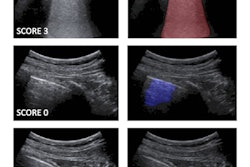

Examples of lung ultrasound images demonstrating the semiautomated detection method of pleural lines. The upper panel (A) shows a confirmed COVID-19 case with pleural thickening and irregularity. Right panel A shows pleural line detected with the semiautomated segmentation. The lower panel (B) shows an example of a normal case where the pleural line is outlined by semiautomated segmentation. Images and caption courtesy of the Journal of the American College of Emergency Physicians.The team found that six of seven p-line features shown in the computer-based technology had a significant difference between normal and COVID-19 cases, the lone exception being brightness. Meanwhile, only two of the seven traditional lung texture features produced such significant differences.